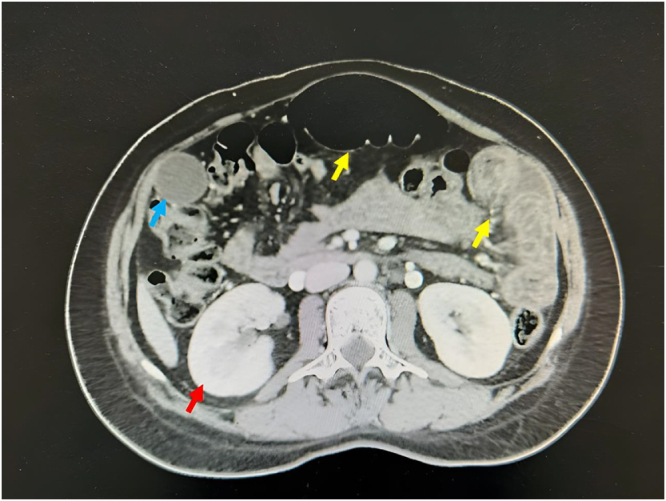

Case presentation: We report the case of a 25-year-old woman with a twin pregnancy who was admitted at 32 weeks of gestation with acute abdominal pain and nausea. Due to persistent severe pain, unexplained intraperitoneal fluid, and progressing labor, an emergent cesarean section was performed. Intraoperatively, 2000 mL of milky white fluid was discovered in the peritoneal cavity. Biochemical analysis with markedly elevated triglycerides confirmed the diagnosis of chylous ascites. Postoperative management included broad-spectrum intravenous antibiotics, octreotide injection, and a low-fat diet supplemented with medium-chain triglyceride oil. By postoperative day 7, ultrasound showed complete resolution of ascites, and the patient was discharged in stable condition. No recurrence was noted during 3 years of follow-up.

Clinical discussion: This report presents a rare case of spontaneous chylous ascites in a previously healthy pregnant woman with a twin gestation. Potential mechanism for chylous ascites in our case can be due to enlarged gravid uterus of twin gestation during late pregnancy, which suppress the abdominal thoracic duct of mother and increase the pressure of the duct. Another possible mechanism involves the physiological effects of progesterone during pregnancy. Progesterone is known to induce smooth muscle relaxation, which can lead to dilation of lymphatic vessels and increased lymphatic flow. This vasodilatory effect may predispose to lymphatic leakage and contribute to the development of chylous ascites. The presence of milky white peritoneal fluid combined with a markedly elevated triglyceride concentration (≥ 110 mg/dL, 1945 mg/dL in our case) was key to confirm the diagnosis of chylous ascites. Treatment strategies typically depends on the underlying etiology and may include dietary modification (low-fat, MCT-enriched diet), pharmacologic therapy (somatostatin or octreotide), and surgical interventions in refractory cases.